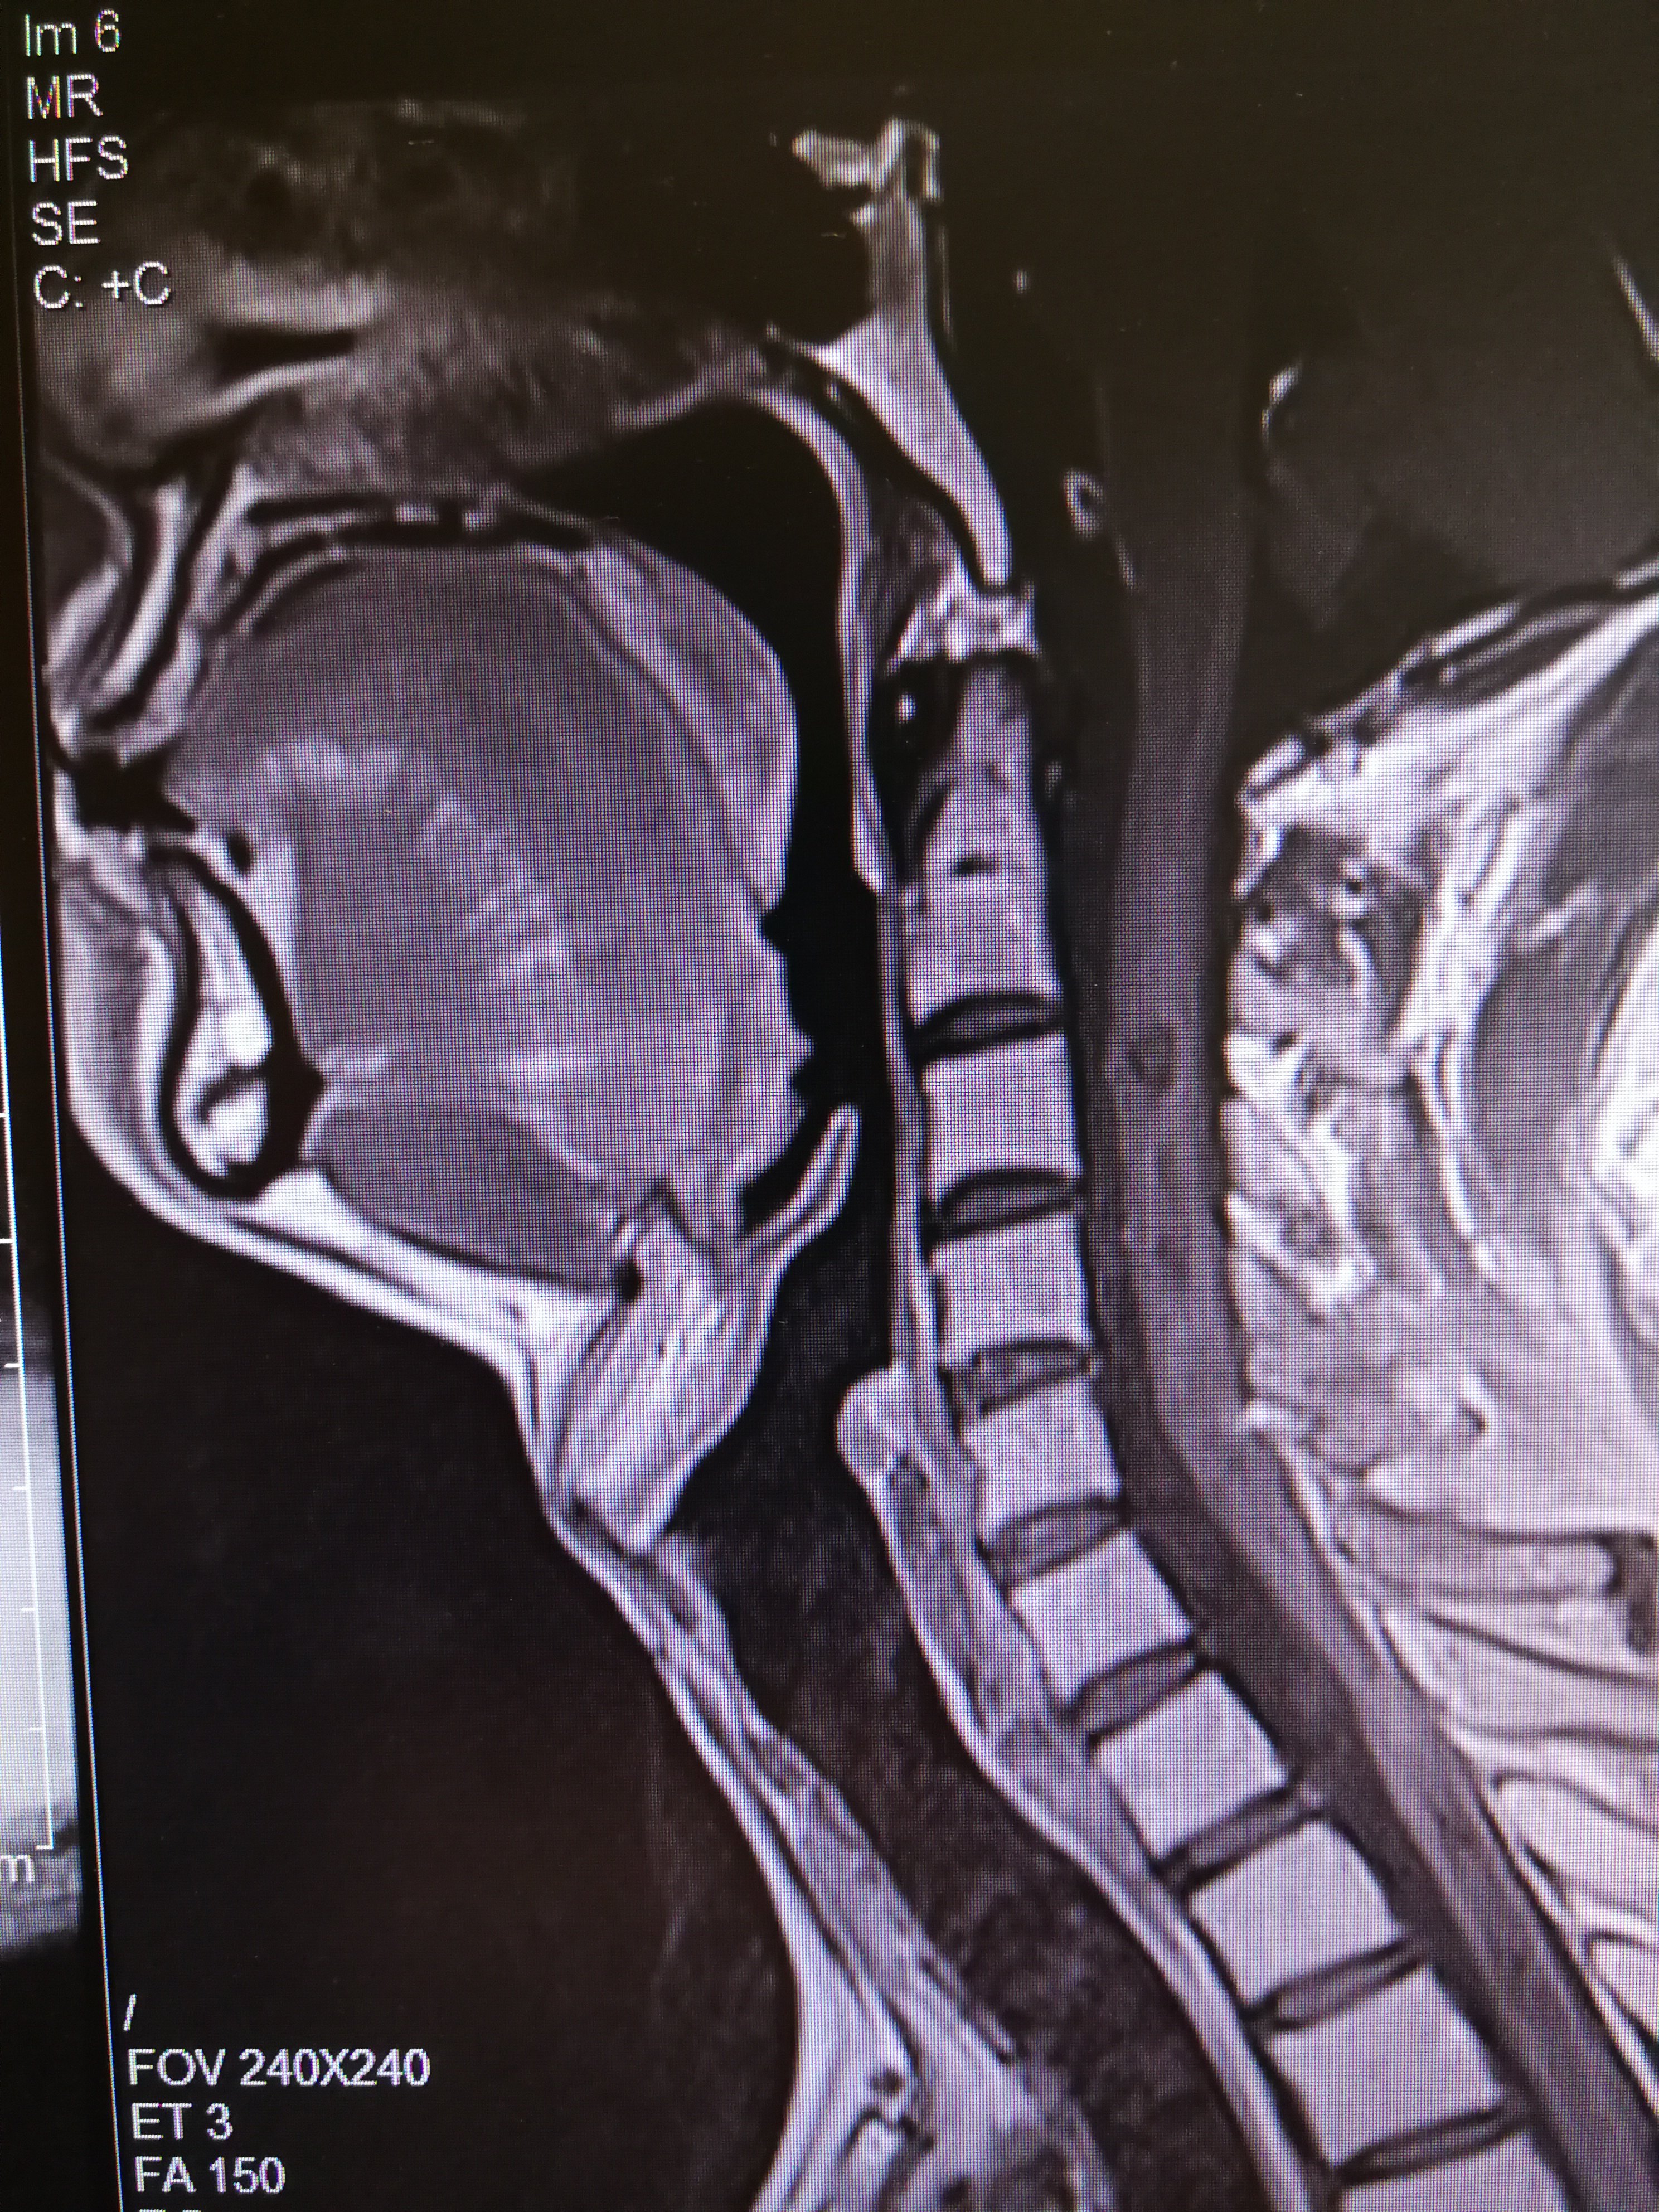

术前颈椎增强mri,提示颈4/5左侧椎间孔及椎管内外哑铃型肿瘤,考虑

图片尺寸792x1181